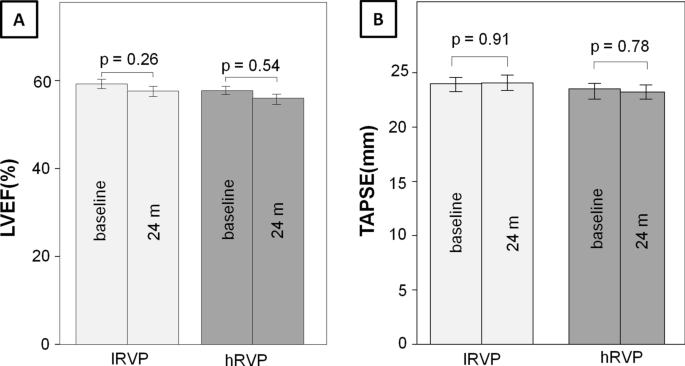

The short term influence of right ventricular pacing burden on echocardiographic and spiroergometric parameters in patients with preserved left ventricular ejection fraction, BMC Cardiovascular Disorders